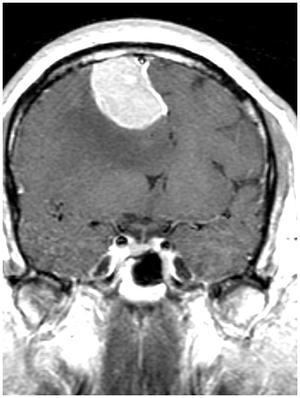

Glioblastoma multiforme:

High grade astrocytic tumor cellular pleomorphism, mitotic activity, necrosis and vascular proliferation

- Diagnositic staining: stain astrocytes for GFAP

- Can cross corpus callosum–> positional headaches (Butterfly glioma on MRI)

Front: pseduopalisading necrosis

Genome-wide analysis of gliomas= somatic mutations of Isocitrate Dehydrogenase 1 (12%)- 5/6 of secondary gliobastomas

Below: vascular proliferation driven by VEGF= diagnostic feature in glioblastoma

- Treated with avastin (Bevacizumab)